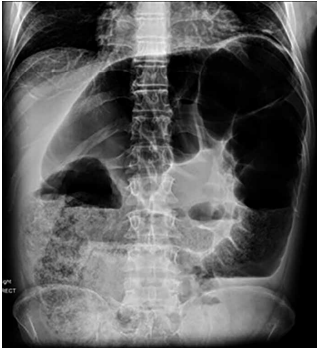

Homem, 76 anos de idade, apresenta dor abdominal, além de estar sem evacuar há 6 dias. Ao exame físico, nota-se dor à palpação e superficial difusa, além de descompressão brusca positiva. Realiza-se a radiografia de abdômen a seguir:

(Arquivo pessoal; imagem usada com autorização)

A hipótese diagnóstica é